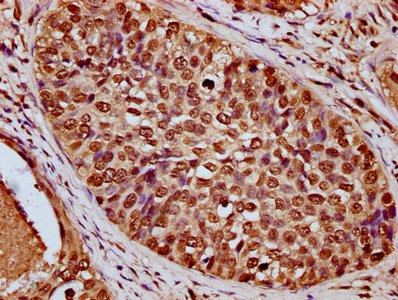

IHC image of CSB-PA010429OA91nbutHU diluted at 1:20 and staining in paraffin-embedded human cervical cancer performed on a Leica BondTM system. After dewaxing and hydration, antigen retrieval was mediated by high pressure in a citrate buffer (pH 6.0). Section was blocked with 10% normal goat serum 30min at RT. Then primary antibody (1% BSA) was incubated at 4°C overnight. The primary is detected by a biotinylated secondary antibody and visualized using an HRP conjugated SP system.